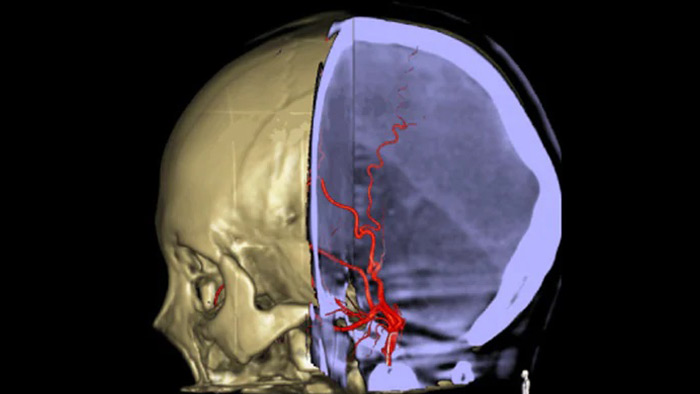

SmartCT Vaso permet de visualiser au-delà du caillot grâce à l’imagerie péri-procédurale de l’aspect des vaisseaux distaux dans les accidents vasculaires cérébraux ischémiques. SmartCT Vaso est une technique basée sur une acquisition Cone Beam CT à faisceau conique et une injection de produit de contraste intra-artérielle. Elle permet la visualisation au-delà du caillot avec l’imagerie péri-procédurale de l’aspect des vaisseaux distaux dans l’accident vasculaire cérébral ischémique. Grâce au remplissage rétrograde, les structures des vaisseaux avant et après le caillot deviennent visibles. SmartCT Vaso 3D Roadmap vous aide à visualiser les dispositifs de retrait de caillot.